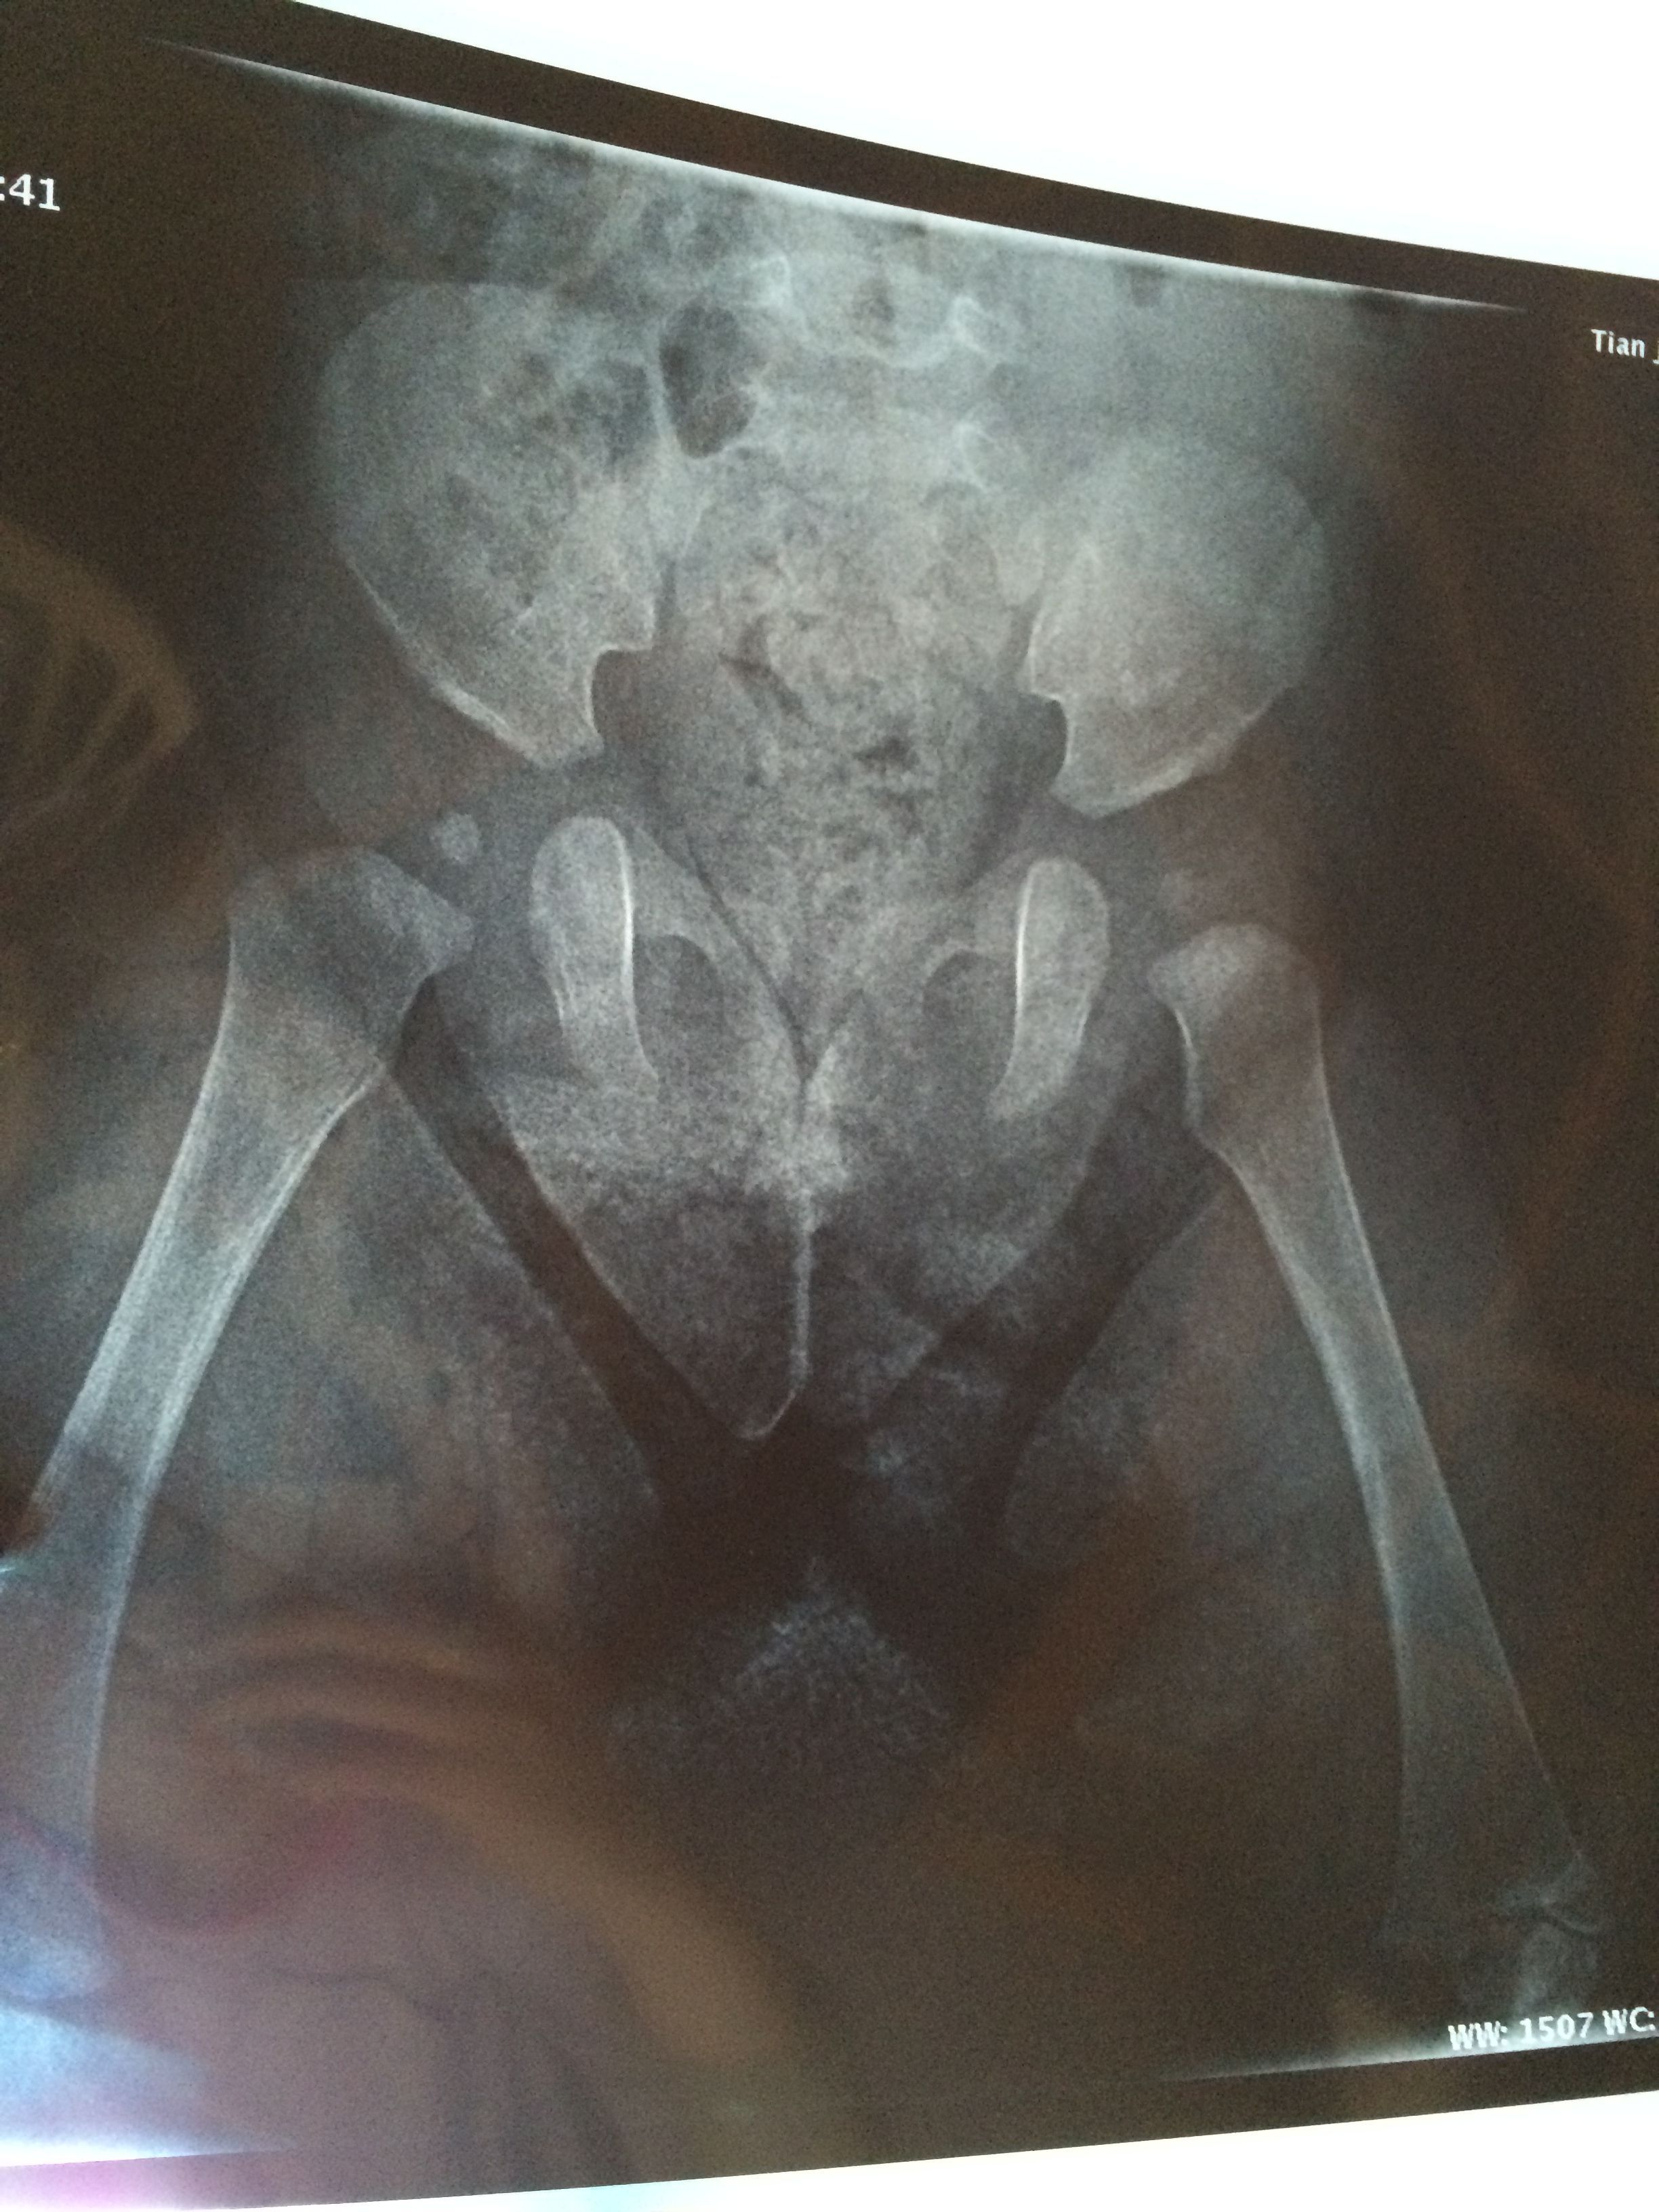

宝宝髋关节发育迟缓(有片),现在戴矫正带,问题大吗 第一张和第二张是4月21号拍的,第三张和第四张是7月7号拍的,骨科医生吩咐说还要带矫正带一个半月,请问如果不戴,髋骨会自己发育好吗?(现在宝宝六个月) 点击展开 匿名用户 2014-07-08 12:43 为您推荐: 其他回答 你好,你这个时候就是要自己注意给宝宝带一些家长气的这样的话只会对宝宝的身体恢复比较好的呢? 可靠的悠闲80 2014-07-08 19:45 相关问题 婴儿髋关节发育迟缓 我的宝宝5个月了 头不能直立 不会自己抓东西 不会吃手 去检查说发育迟缓 该怎么办 两个半月宝宝双侧髋关节发育迟缓角左侧a角56,b角67,右侧a角57 b角64